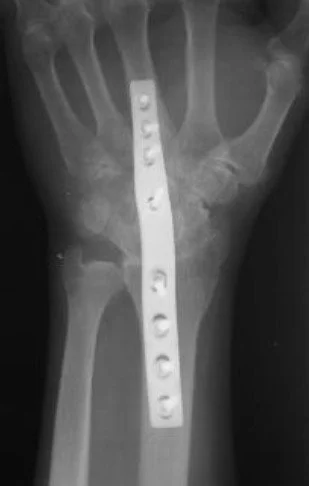

Arthritis Wrist and Forearm Childrens Wrist Fractures Colles Fractures Colles Surgery Chronic Forearm Compartment Syndrome De Quervains Syndrome Kienbocks Disease Scaphoid Fractures Scpholunate Ligament Tears TFC Tears Wrist Arthritis - Salvage Procedures Wrist Arthroscopy Wrist Exercises Wrist Xrays - Radiographers